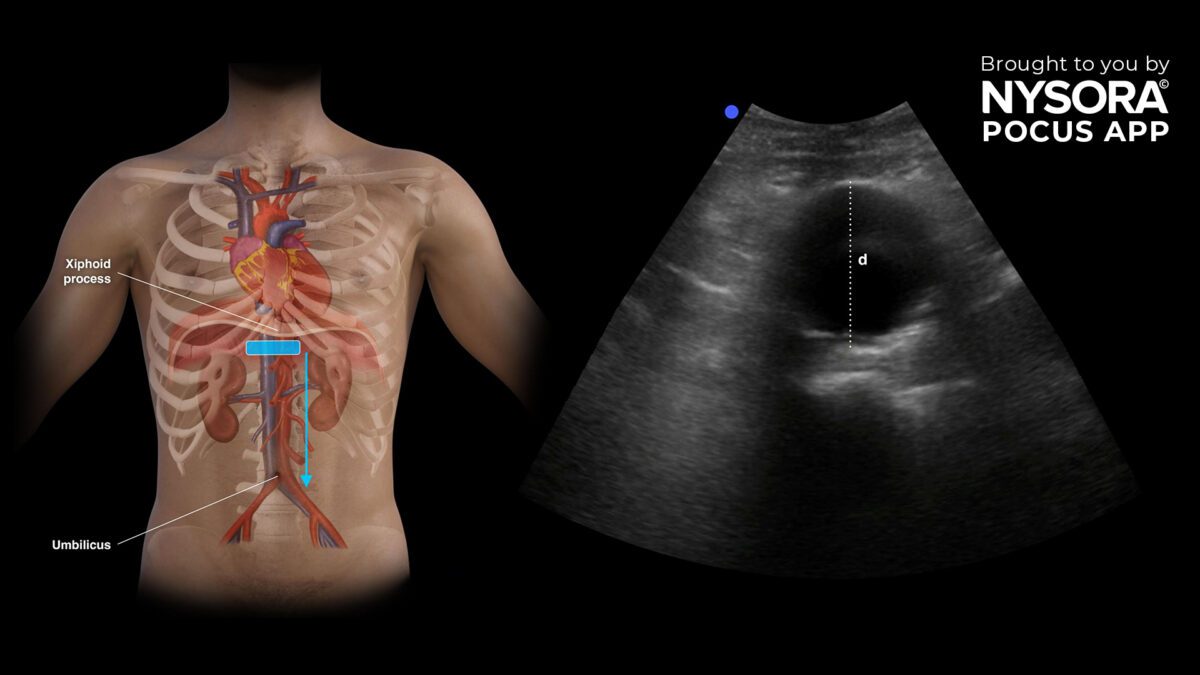

همه افراد شرکتکننده در این مطالعه از قبل دچار این بیماری بودند و تحت نظر قرار داشتند. پژوهشگران میزان ماده TMAO را در خون آنها اندازهگیری کردند و با استفاده از سونوگرافی یا سیتیاسکن، روند رشد آنوریسمها را مورد بررسی قرار دادند.